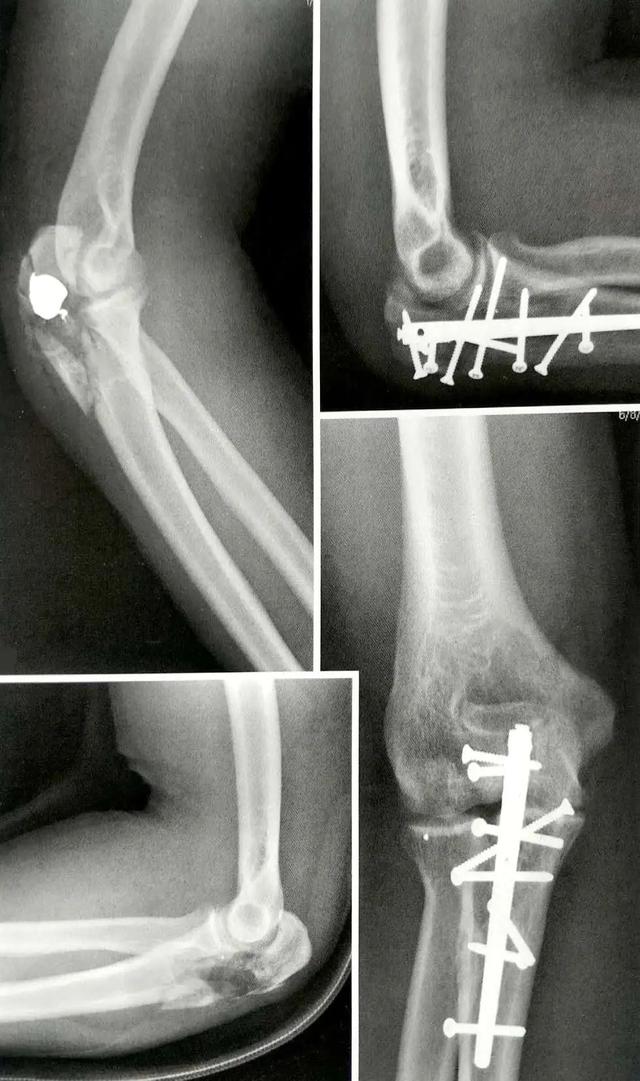

A:鹰嘴骨折脱位

B:用钢板和拉力螺钉固定鹰嘴的骨折脱位

C:用拉力螺钉和钢板固定鹰嘴骨折脱位

钢板可提供骨折愈合及早期活动度练习所需的所有稳定性,这样可最大限度地提高功能恢复。

钢板内固定最常见的缺点是内固定物存留引起症状。但很多近期的报道否定了这点。新型模板预弯钢板很薄,可于近端提供更多的螺钉选择,有锁定螺钉功能,且有匹配尺骨近端解剖外形的弧度而适用于延伸的骨折。